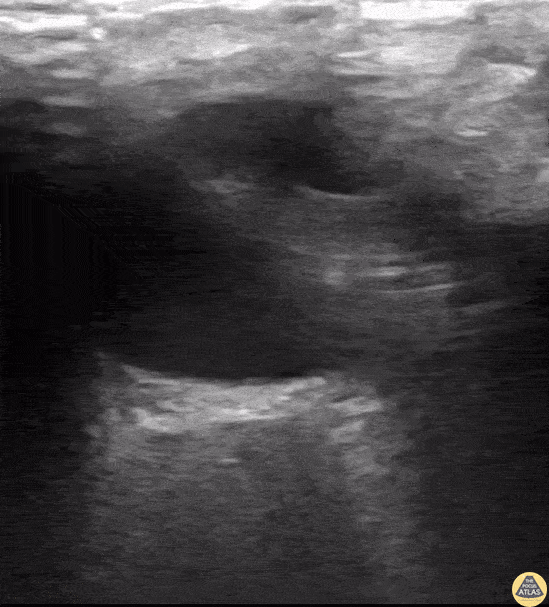

A 24-year old male presented to the ED with a six-month history of progressive total right vision loss. A bedside ocular ultrasound examination was performed that revealed an elevated optic disc with enlarged ONSD measuring 9.7mm, consistent with papilledema. An MRI of the head confirmed an enlarged intraconal portion of the right optic nerve, consistent with glioma. Marko Lubardic, MS4; Tom Taugher, DO, PGY3; Michael Bernard, DO, PGY1; Central Michigan University Emergency Medicine Residency